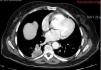

Presentamos el caso de una paciente de 72 años de edad sin antecedentes de interés que consultó en urgencias por un cuadro de 2 semanas de evolución de alteración de la marcha, cefalea y vómitos. El TAC craneal reveló la presencia de hidrocefalia obstructiva secundaria a una lesión pineal con impronta en el tercer ventrículo. La resonancia magnética mostró, además de la lesión ya referida, otra más pequeña situada en el foramen de Lushcka derecho. Se llevó a cabo una ventriculostomía endoscópica del suelo del tercer ventrículo y la biopsia endoscópica de la lesión, cuyo resultado fue de metástasis compatible con carcinoma de pulmón. Se realizó un TAC toracoabdominopélvico que mostró una masa pulmonar compatible con el carcinoma primario. Se decidió tratamiento sistémico de la enfermedad. La paciente falleció 2 meses tras el diagnóstico.

A 72-year-old female with no relevant medical history consulted in the emergency room for a two-week history of headache, vomiting and gait disturbance. Head CT scan revealed obstructive hydrocephalus secondary to a pineal mass with compression of the third ventricle. Magnetic Resonance showed another mass located in the right Lushcka foramen. Endoscopic third-ventriculostomy and biopsy of pineal mass were performed. Pathological analysis was consistent with metastasis of carcinoma. Full-body CT scan showed a lung mass related to primary carcinoma. The patient received systemic treatment for metastatic lung cancer. She died two months after diagnosis.